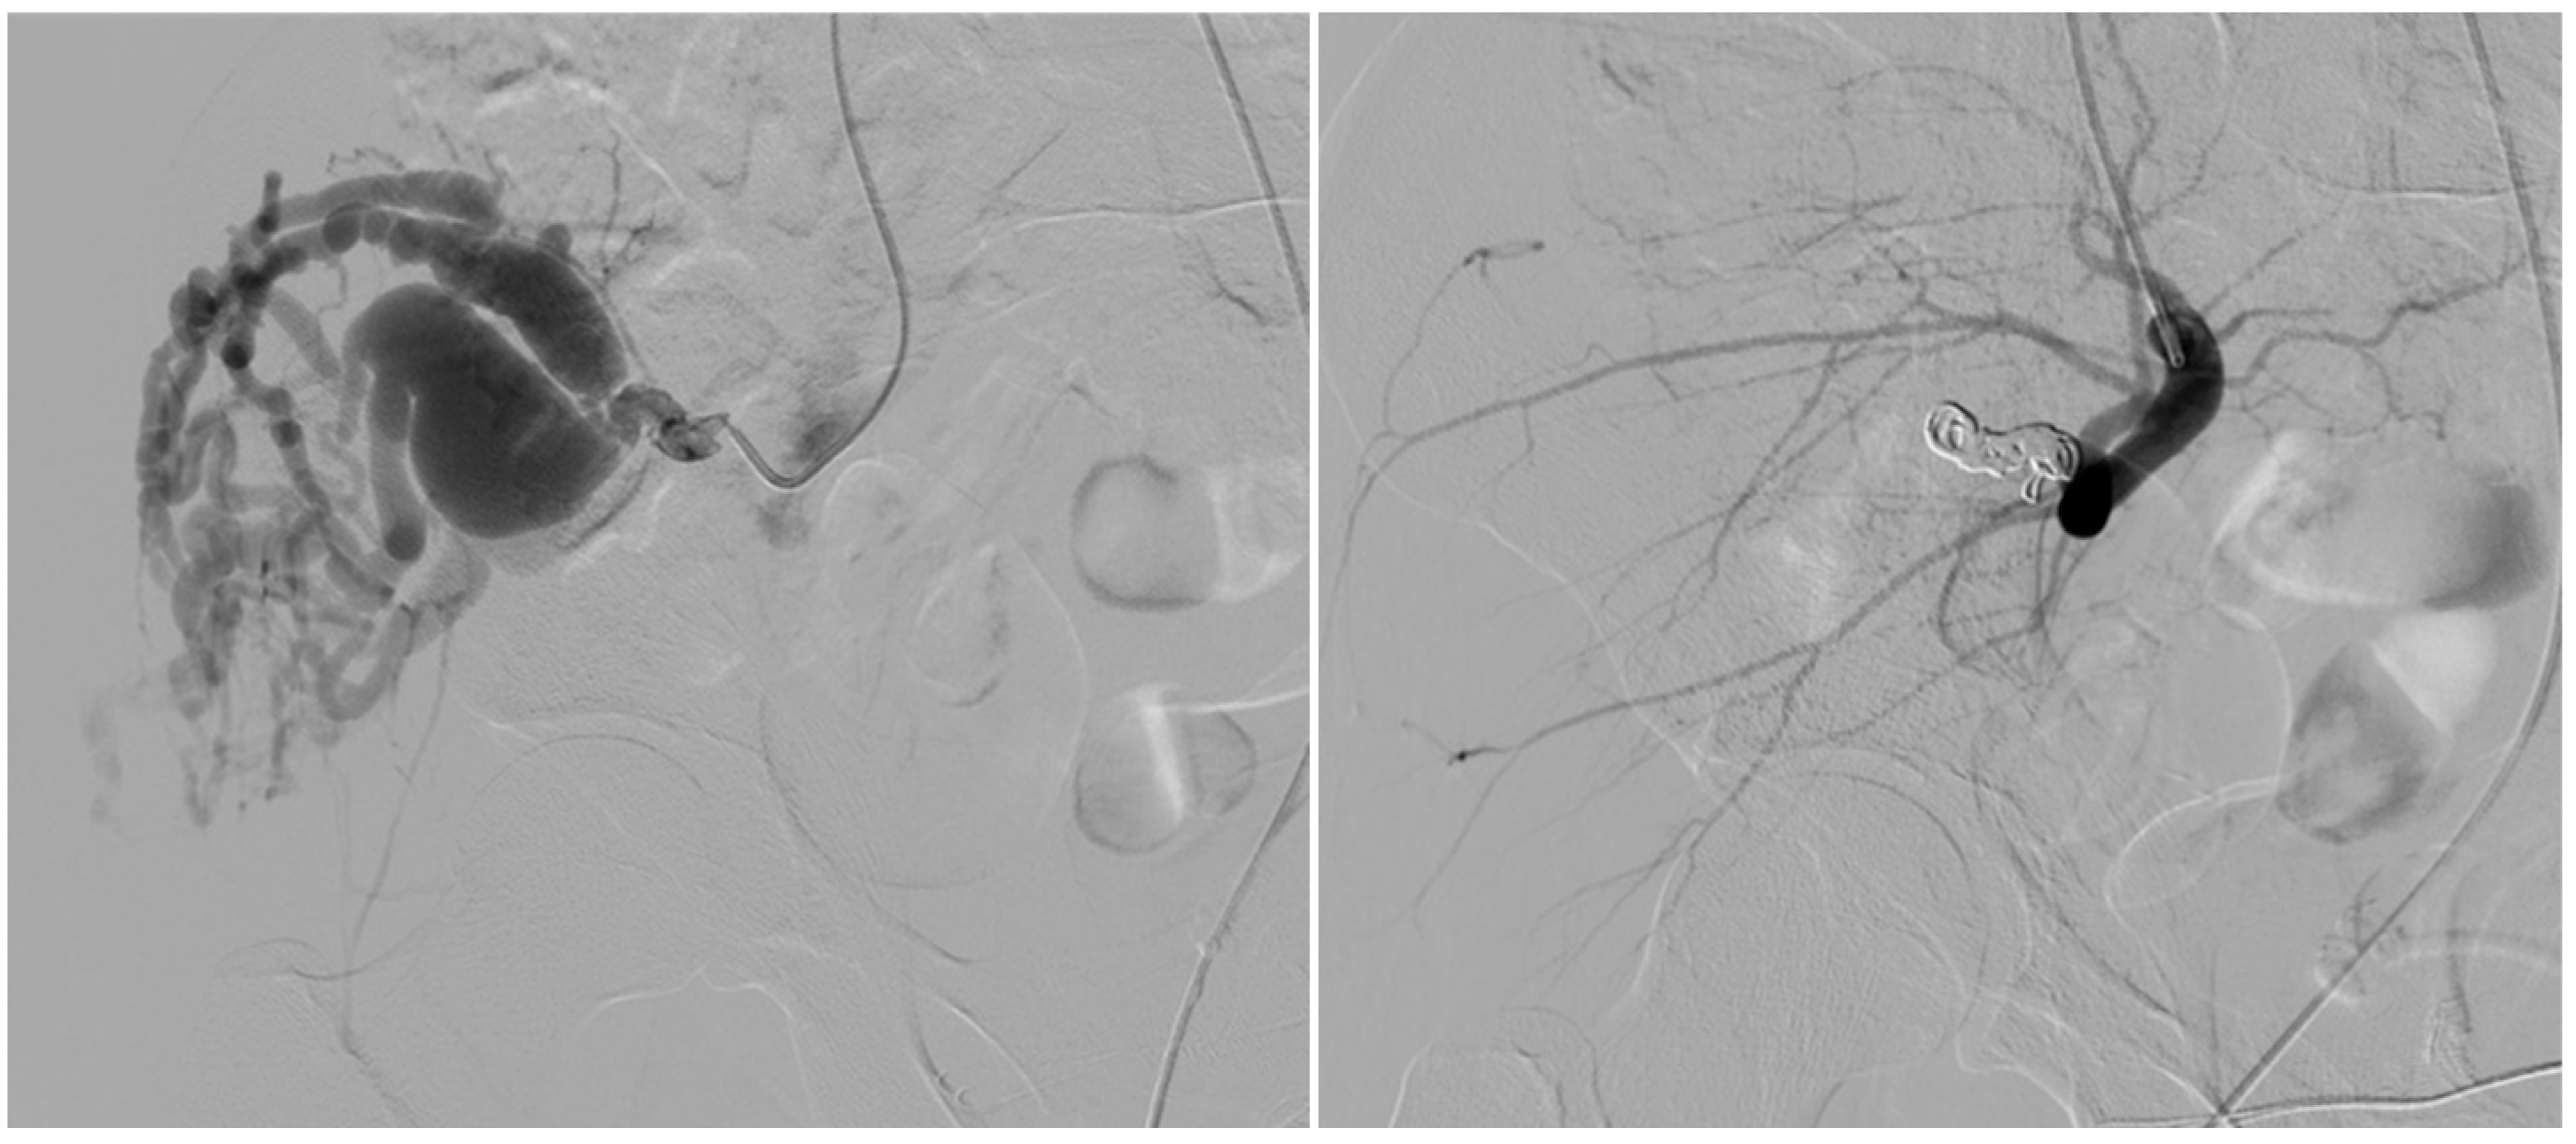

- Arterial embolization was preferred in lesions with limited and accessible feeders.

- Venous embolization was favored when the dominant outflow vein (DOV) was accessible and formed the site of arteriovenous shunting.

- Combined arterial and venous embolization was used in complex lesions with multilevel shunting, high-flow recurrence, or partial response to single-route embolization.